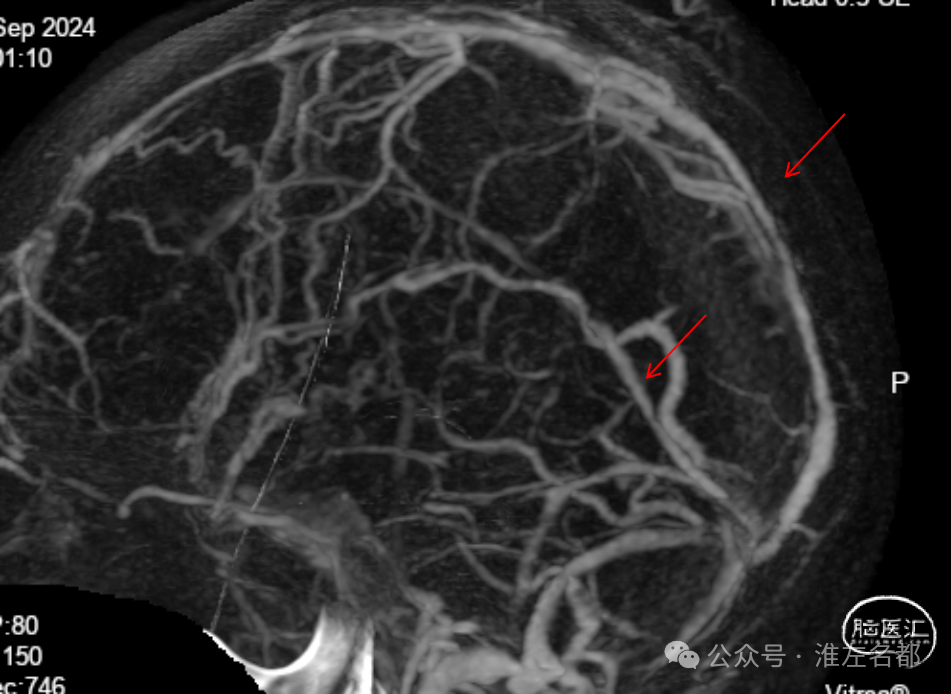

增强MRV:左侧横窦-乙状窦显影纤细;上矢状窦和右侧横窦-乙状窦充盈缺损;脑深部静脉和直窦未见显影。

SWI:双侧丘脑渗血改变,右侧基底静脉和大脑中静脉血栓。

三维黑血高分辨T1平扫(上图)和增强(下图):右侧乙状窦慢性血栓,平扫呈等低信号,并显著强化。

三维黑血高分辨T1平扫(上图)和增强(下图):右侧横窦慢性血栓。

三维黑血高分辨T1平扫(上图)和增强(下图):上矢状窦慢性血栓;直窦内新进血栓(急性血栓等低信号,或亚急性血栓高信号,无强化)。

三维黑血高分辨T1平扫(上图)和增强(下图):左侧横窦发育细小。

三维黑血高分辨T1平扫(上图)和增强(下图):左侧乙状窦局部未发育。